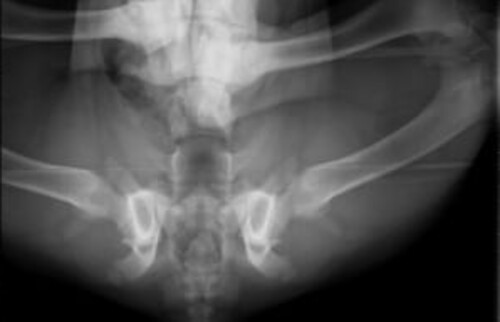

Bilder einer vollständigen Hüftdysplasie-Untersuchung beim Hund

In unserer Tierklinik bei Karlsruhe können unsere Ärzt*innen durch die Aufnahmen eine zuverlässige Prognose für die Weiterentwicklung der Hunde-Hüfte stellen.

Schwarz-weißes Röntgenbild der Hüftgelenke und des Beckens eines Hundes in der Aufsicht.